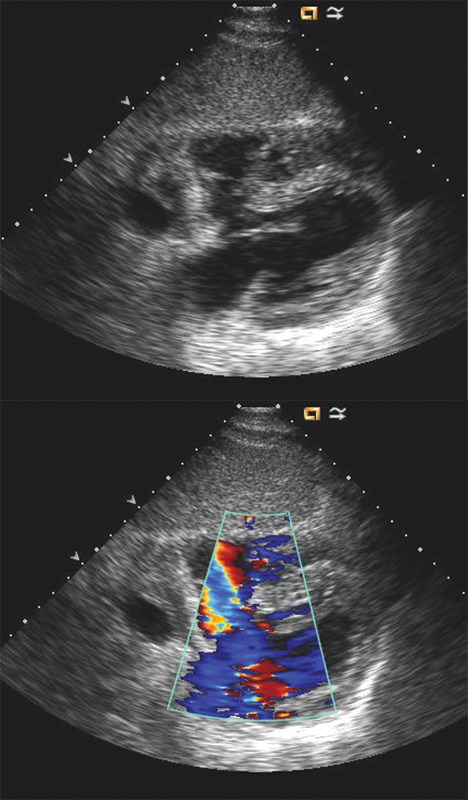

فحوصات تشخيصية لبعض امراض القلب والشرايين التاجية